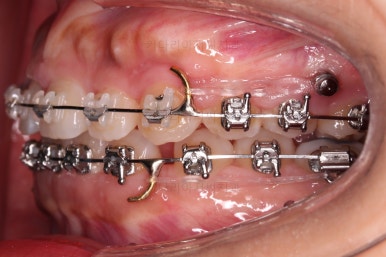

위쪽은 미니스크류 위치를 바꿔줘 교합을 맞춰주고요.

아래쪽은 마찬가지로 미니스크류를 비대칭으로 식립해서 어금니를 당겨줍니다.

계속 당겨줍니다.

위아래 치열의 중앙이 서서히 맞아지는 느낌이 드시나요?

조금만 더 하면 되겠네요.

중앙선을 맞추고 교합도 잘 맞추고 마무리를 합니다.